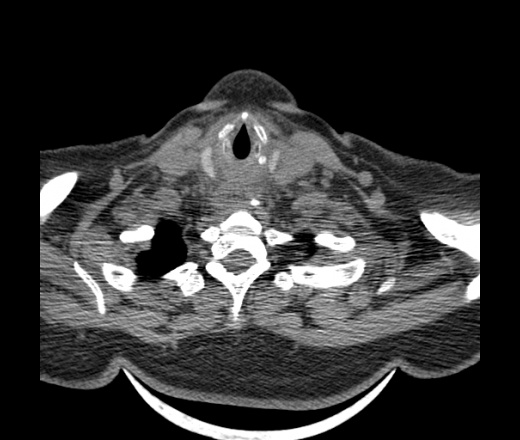

Женщина поступила в х/о спустя 4 дня после того как при употреблении карася подавилась костью.

Наличие газа в средостении на протяжении тел С2-С6 (медиастинальна эмфизема); рыбная кость на уровне тела С6.

При всем уважении, но говорить о медиастинальной эмфиземе, оценивая мягкие ткани шеи, как-то слишком резко. На мой взгляд, это ретрофарингеальное пространство.

Эвакуировали почти 100мл гноя. Но кость не смогли найти. Думаю что она даст дальнейшее ослоднение. Эндоскопически за черпалонадгортаной звязкой не смогли зайти в пищевод, все мягкие ткани отечные, просвет пищевода сдавлен. По всей видимости параэзофагеальная клетчака тоже задействована. Эмпиема, если ее можно так назвать, незнаю как правильно дошла до уровня яремной вырезки. Чем закончиться напишу. Ждем медиастинита.

Флегмона заглоточного пространства шеи, только операция, флегмоны вскрывают. Риск медиастинита.

Согласен с Вами; конечно, наличие газа в клетчатке ретрофарингеального пространства (затмение с опечаткой..). К сожалению, процесс "продвигается" к медиастиниту. Но почему никто, не отмечает наличие рыб. кости; или это для Всех очевидно?